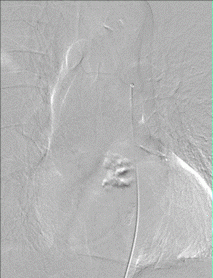

GIF of pinal angiogram

Figure 3. Spinal angiogram - demonstrating a thoracic Spinal Type I Spinal Dural Fistula with dilated veins abnormally filling inside the spinal canal

• Spinal MRI – This test is typically the first study ordered when a spinal vascular malformation is suspected. Spinal MRIs can demonstrate abnormal enlarged vessels, abnormal spinal cord changes and give important clues about the presence and location of the vascular malformation.

• Spinal angiogram – This exam is the gold standard for confirming the presence of a spinal vascular malformation, characterizing the malformation, and demonstrating its exact location in the spinal canal (Figure 3). This imaging study is used to best understand the anatomy of the malformation so the appropriate treatment option can be determined.